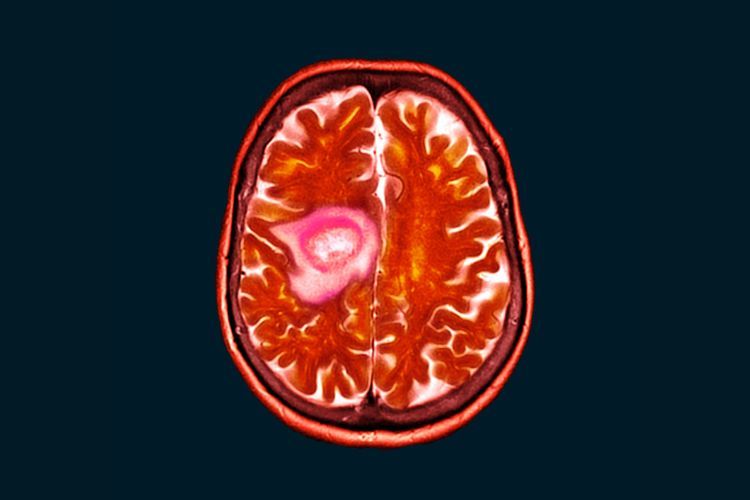

Glioblastom je agresivni tumor mozga koji se razvija iz glijalnih ćelija, koje podržavaju i štite nerve u centralnom nervnom sistemu. Ovo je najčešći i najsmrtonosniji tip primarnih tumora mozga kod odraslih. Glioblastom može brzo rasti i širi se u okolno tkivo, što otežava potpuno uklanjanje hirurškim putem.

• CT skeniranje - Komjuterska tomografija može pokazati prisustvo tumora i njegovu lokaciju.

• MR - Magnetna rezonanca pruža detaljnije slike mozga i pomaže u proceni veličine i vrste tumora.

Glioblastom, ili GBM, je najagresivniji oblik malignog tumora mozga. Pripada kategoriji glioma i klasifikovan je kao IV stepen prema Svetskoj zdravstvenoj organizaciji (SZO). Raste brzo i invazivno, zahvatajući okolno moždano tkivo, što ga čini teško izlečivim.

Magnetna rezonanca je neinvazivna dijagnostička tehnika koja koristi magnetna polja i radio talase za stvaranje detaljnih snimaka unutrašnjih organa i tkiva u telu. MRI je kritična u dijagnostici, praćenju i planiranju tretmana za tumore mozga kao što je glioblastom.